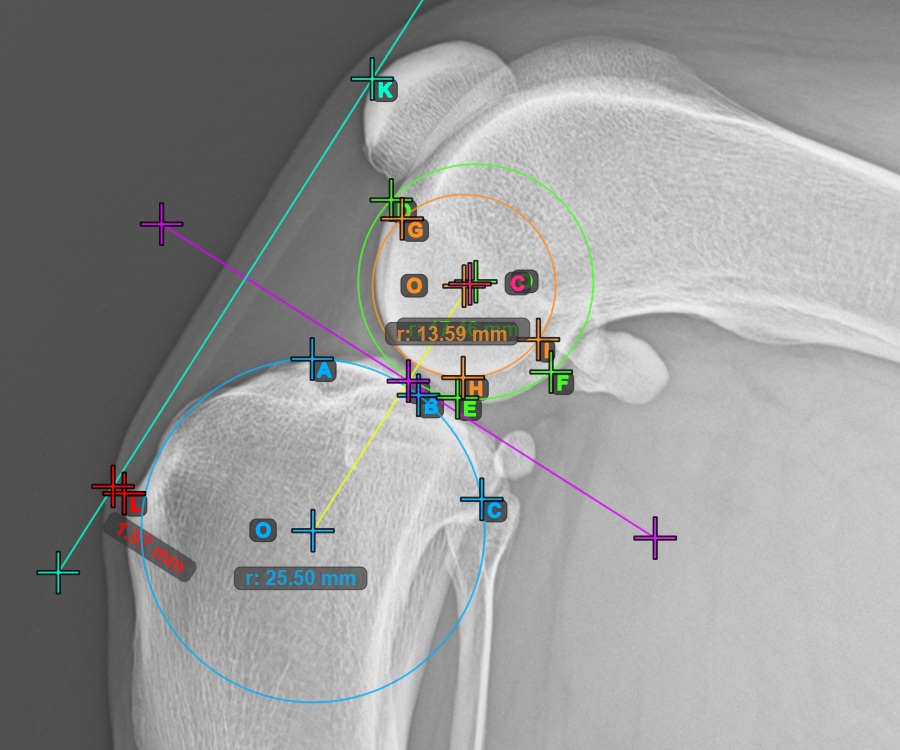

Folytassa a mérést az első Condylus Femoris ízületi felszínén lévő három pont megjelölésével.

Jelölje meg a három pontot a combcsont fő condylusán (Condylus Femoris). A sorrendtől függetlenül ügyeljen arra, hogy megjelölje a legfelső pontot, a legalacsonyabb pontot és a Condylus Femoris középpontját. A három pont alapján a rendszer automatikusan létrehoz egy kört.

A lenti kép az első Condylus Femoris-on elhelyezett három pont tipikus elhelyezkedését ábrázolja.

Ezen felül jelölje meg a három pontot a második Condylus Femoris ízületi felszínén.

Jelölje meg a három pontot a combcsont belső (másodlagos) condylusán (Condylus Femoris). A sorrendtől függetlenül ügyeljen arra, hogy megjelölje a legfelső pontot, a legalacsonyabb pontot és a Condylus Femoris középpontját. A három pont alapján a rendszer automatikusan létrehoz egy kört.

A lenti kép a második Condylus Femoris-on elhelyezett három pont tipikus elhelyezkedését ábrázolja.

Jelöljön meg egy pontot az ízület előtt a két fő condylus kör közötti közös tangensen. Egy vonal automatikusan áthalad a megjelölt ponton.

A lenti kép a két kör közötti közös tangensen elhelyezett pont tipikus elhelyezkedését ábrázolja.